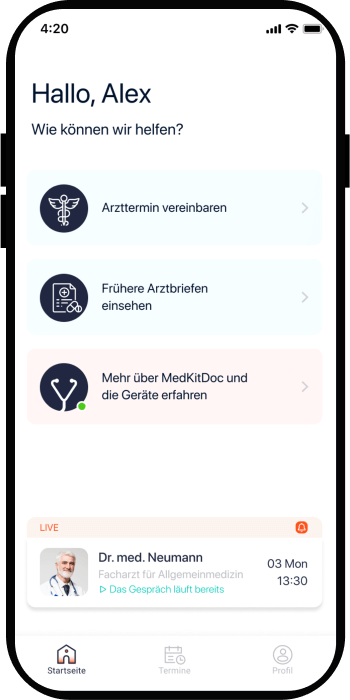

Following our team expertise in healthcare products, we’ve outlined clear & clean UX concepts and started with careful UI creation leveraging native mobile technologies capabilities.

One of the main differentiators in Healthcare is the UX of the product – many companies develop functional telemedicine apps but they often lack clear & simple UX with sophisticated design in place – that what Interexy’s team focused on during the design process.

We also knew that the design should be robust & responsive to the standards of B2B healthcare space – here at Interexy we did research on competitive telemedicine products taking the best UI & UX solutions and applying them with MedKitDoc.

One of the challenges with the UX part of the product was creating a separate flow for physicians & adapting it to the standards of healthcare software tools making the design beautiful and clean at the same time.

Many healthcare products that being used by practicing physicians nowadays lack simplicity & beautiful UX and UI solutions and with MedKitDoc we had a goal to disrupt industry standards and create an iOS app that will distinguish itself from the similar products in the industry with its’ modern design approach.

Implementation of design pixel-perfectly & connection of the UI with the user experienced outlined by clickable prototype provided at the completion of design stage were the most important points during the UI implementation part of the project.

We set a high-end goal with changing how healthcare is treating the user experience & user interface with the software products and apps especially and wanted to provide similar to popular social apps type of user experience.